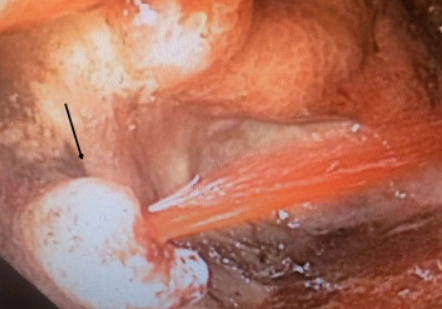

• Giả phình động mạch túi mật (Cystic Artery Pseudoaneurysm - CAP)

• Giả phình mạch quanh tụy (Peripancreatic Pseudoaneurysm)